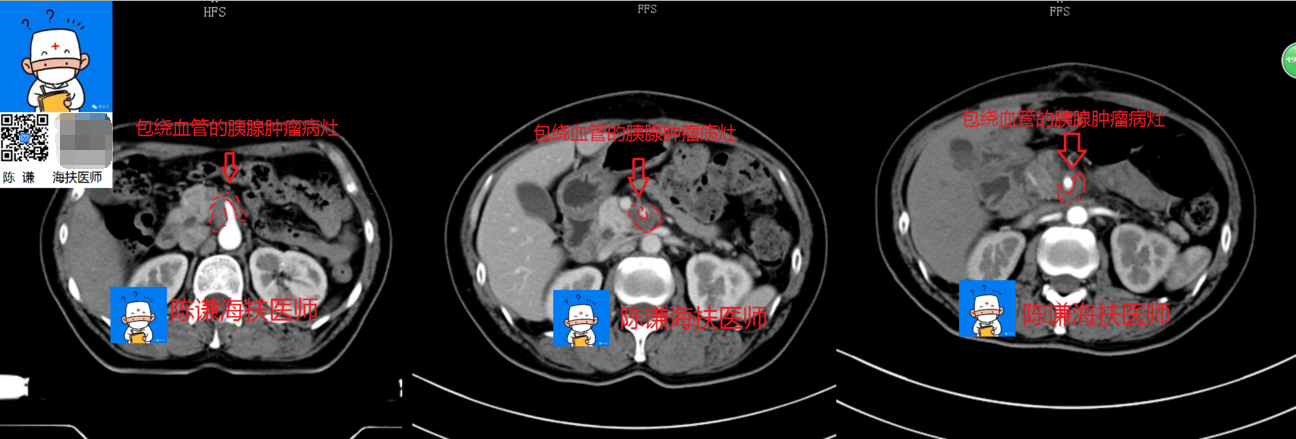

胰腺癌的海扶治疗 - 好大夫在线